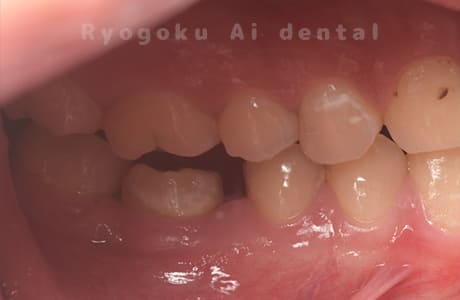

Case02

-

- 原因

- C4

- 治療期間

- 3ヶ月

- 治療内容

- 自家歯牙移植手術+マイクロエンド+ダイレクトボンディング

- 治療費用

- 220,000円

他院で虫歯が大きく、抜歯と判断され、インプラント手術を提案された患者様です。親知らずが残存していたため、自家歯牙移植手術を行いました。

<リスク・副作用>

治療後、痛みや違和感、出血、腫れなどが出る事があります。喫煙者、糖尿病などの方の場合、歯が生着しない場合があります。